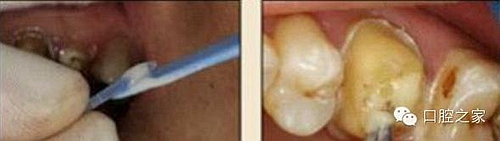

11. 吸取根管內(nèi)多余的粘結(jié)劑

根管內(nèi)涂抹粘接劑時,理想的粘接劑層厚度應(yīng)為25μm~40μm,厚度增加或不均勻不僅導致粘接強度的下降,也不利于纖維樁在根管內(nèi)的暢通就位。其次,多余粘接劑的存在往往會加速樹脂水門汀的固化速度,使纖維樁無法及時就位而導致粘接失敗。根管內(nèi)涂抹粘接劑較規(guī)范的操作應(yīng)該是,毛刷蘸取粘接劑在根管內(nèi)反復(fù)涂擦20s,涂抹2-3層(圖 22),然后用紙尖吸取干凈(圖 23),氣槍吹 5s使粘接劑中的溶劑快速揮發(fā)。在該操作步驟中,大錐度紙尖的應(yīng)用非常關(guān)鍵,也往往被很多醫(yī)生忽視,它不僅可以吸取多余粘接劑,同時也可使粘接劑在根管內(nèi)鋪展均勻。

圖22:粘接劑涂擦20s,涂抹2-3層。 圖23:紙尖吸出多余粘接劑。